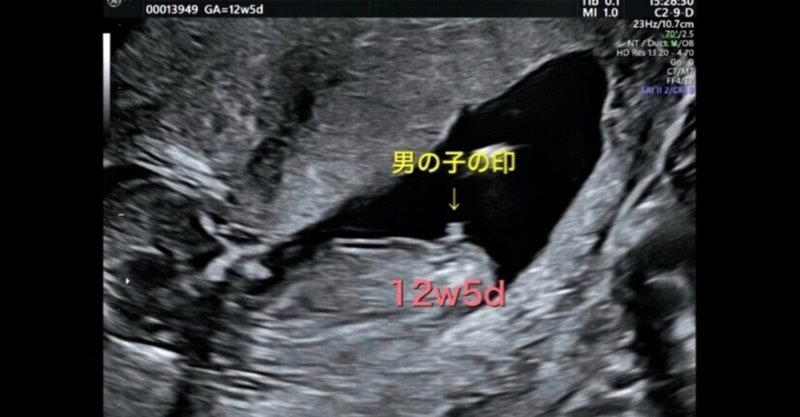

01/09/19 · キレイにすべてのパーツが見えたそうです。(将来はこの画像は秘密にしてあげよう。笑) これがエコー写真で女の子と判断されるものらしいです。 確かに、他のエコー写真で男の子だったら、もっと男子の象徴が大きく映ってたりしますよね。 ドクターいわく、これは確実に女の22/10/18 · この時期の胎児は、大きさが110~140ミリ、体重が60~1グラムとまだまだ小さく、 エコー検査で映る画像での確実な判定は難しいです。 はっきりわかるのは、 赤ちゃんが600~1000グラムになる妊娠24週目(妊娠7ヶ月)以降 といわれています。22/10/19 · 赤ちゃん育児無料イラストフリー素材 2 赤ちゃんのイラスト かわいいフリー素材集 いらすとや 赤ちゃんのイラストbaby無料イラストフリー素材 赤ちゃんのイラストハイハイ かわいいフリー素材集 いらすとや 赤ちゃんのかわいい無料イラスト13選画像サイトまとめ 育児ネット フリーイラ

胎児 エコー 男の子 画像-22/09/ · 胎児 顔 エコー写真=>胎児 エコー 男の子 画像 ~ ベビー 妊娠25週目 25w0d 6d のエコー写真とエピソード 妊娠7ヶ月 Cozre 胎児 顔 エコー写真 初の4dエコーで 赤ちゃんの顔が愛する旦那 性別は男の子かなぁ?女の子かなぁ? と、ドキドキしながら妊婦健診に行ってきました。 妊娠15週0日目の2D&4D19週で判明!胎児の体勢によるかも 上の子は男の子ですが、はっきり言われたのは7ヶ月の時でした。 それまでなぜか検診の時は横向きとかだったんですよね。 下の子は女の子でしたが、19週で4dで診てもらった時、先生に「女の子だね!」と断言されました。

ゆみこさんのブログです。最近の記事は「卵膜付着による胎児発育不全 34w2d1360gの男の子出産」です。 38歳夢クリ→39歳出産→40歳第二子チャレンジ今43歳 ホーム ピグ アメブロ 芸能人ブログ 人気ブログ Ameba新規登録(無料) ログイン 38歳夢クリ→39歳出産→40歳第二子チャレンジ今43歳赤ちゃん 男の子 359 プリ画像には、赤ちゃん 男の子の画像が359枚 、関連したニュース記事が25記事 あります。 一緒に ペア画、 男性イラスト、 女の子 後ろ姿 も検索され人気の画像やニュース記事、小説がたくさんあります。胎児が男の子であれば、さらに成長とともに陰嚢(いんのう)も見られるようになるでしょう。 ただし、女の子のへその緒が男の子の外性器のように見えてしまうケースや、胎児の姿勢の関係で下腹部が写らないケースもあるため、 画像だけで性別を正しく判別できるとは限りません 。